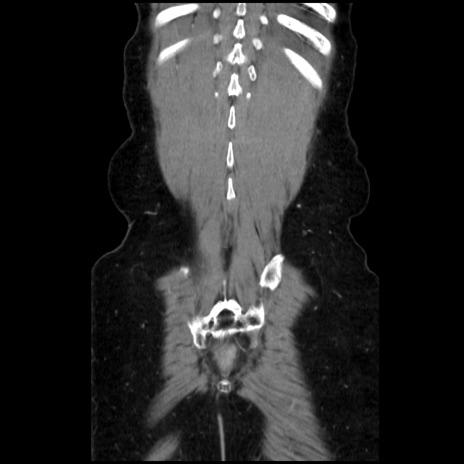

矢状断像